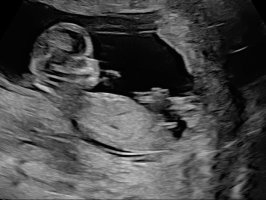

Noen som vil tippe? 13+1. JM klarte ikke si noe sikkert, har bestilt ny UL om 10 dager, kjenner jeg bare må vite

Ser ut som en jente

Dette må være en jente. Nub har ikke antydning til vinkel en gang.